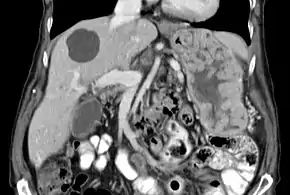

Biopsy of the stomach in Ménétrier disease showing the substantial pit hyperplasia makes the large rugal folds appear to be covered by myriad polyps resembling hyperplastic polyps. The muscularis propria is the folded structure at the bottom center. | |

With Ménétrier disease, the stomach is characterized by large, tortuous gastric folds in the fundus and body, with the antrum generally spared, giving the mucosa a cobblestone or cerebriform (brain-like) appearance.[5] Histologically, the most characteristic feature is massive foveolar hyperplasia (hyperplasia of surface and glandular mucous cells).[3] The glands are elongated with a corkscrew-like appearance and cystic dilation is common. Inflammation is usually only modest, although some cases show marked intraepithelial lymphocytosis. Diffuse or patchy glandular atrophy, evident as hypoplasia of parietal and chief cells, is typical.[4]